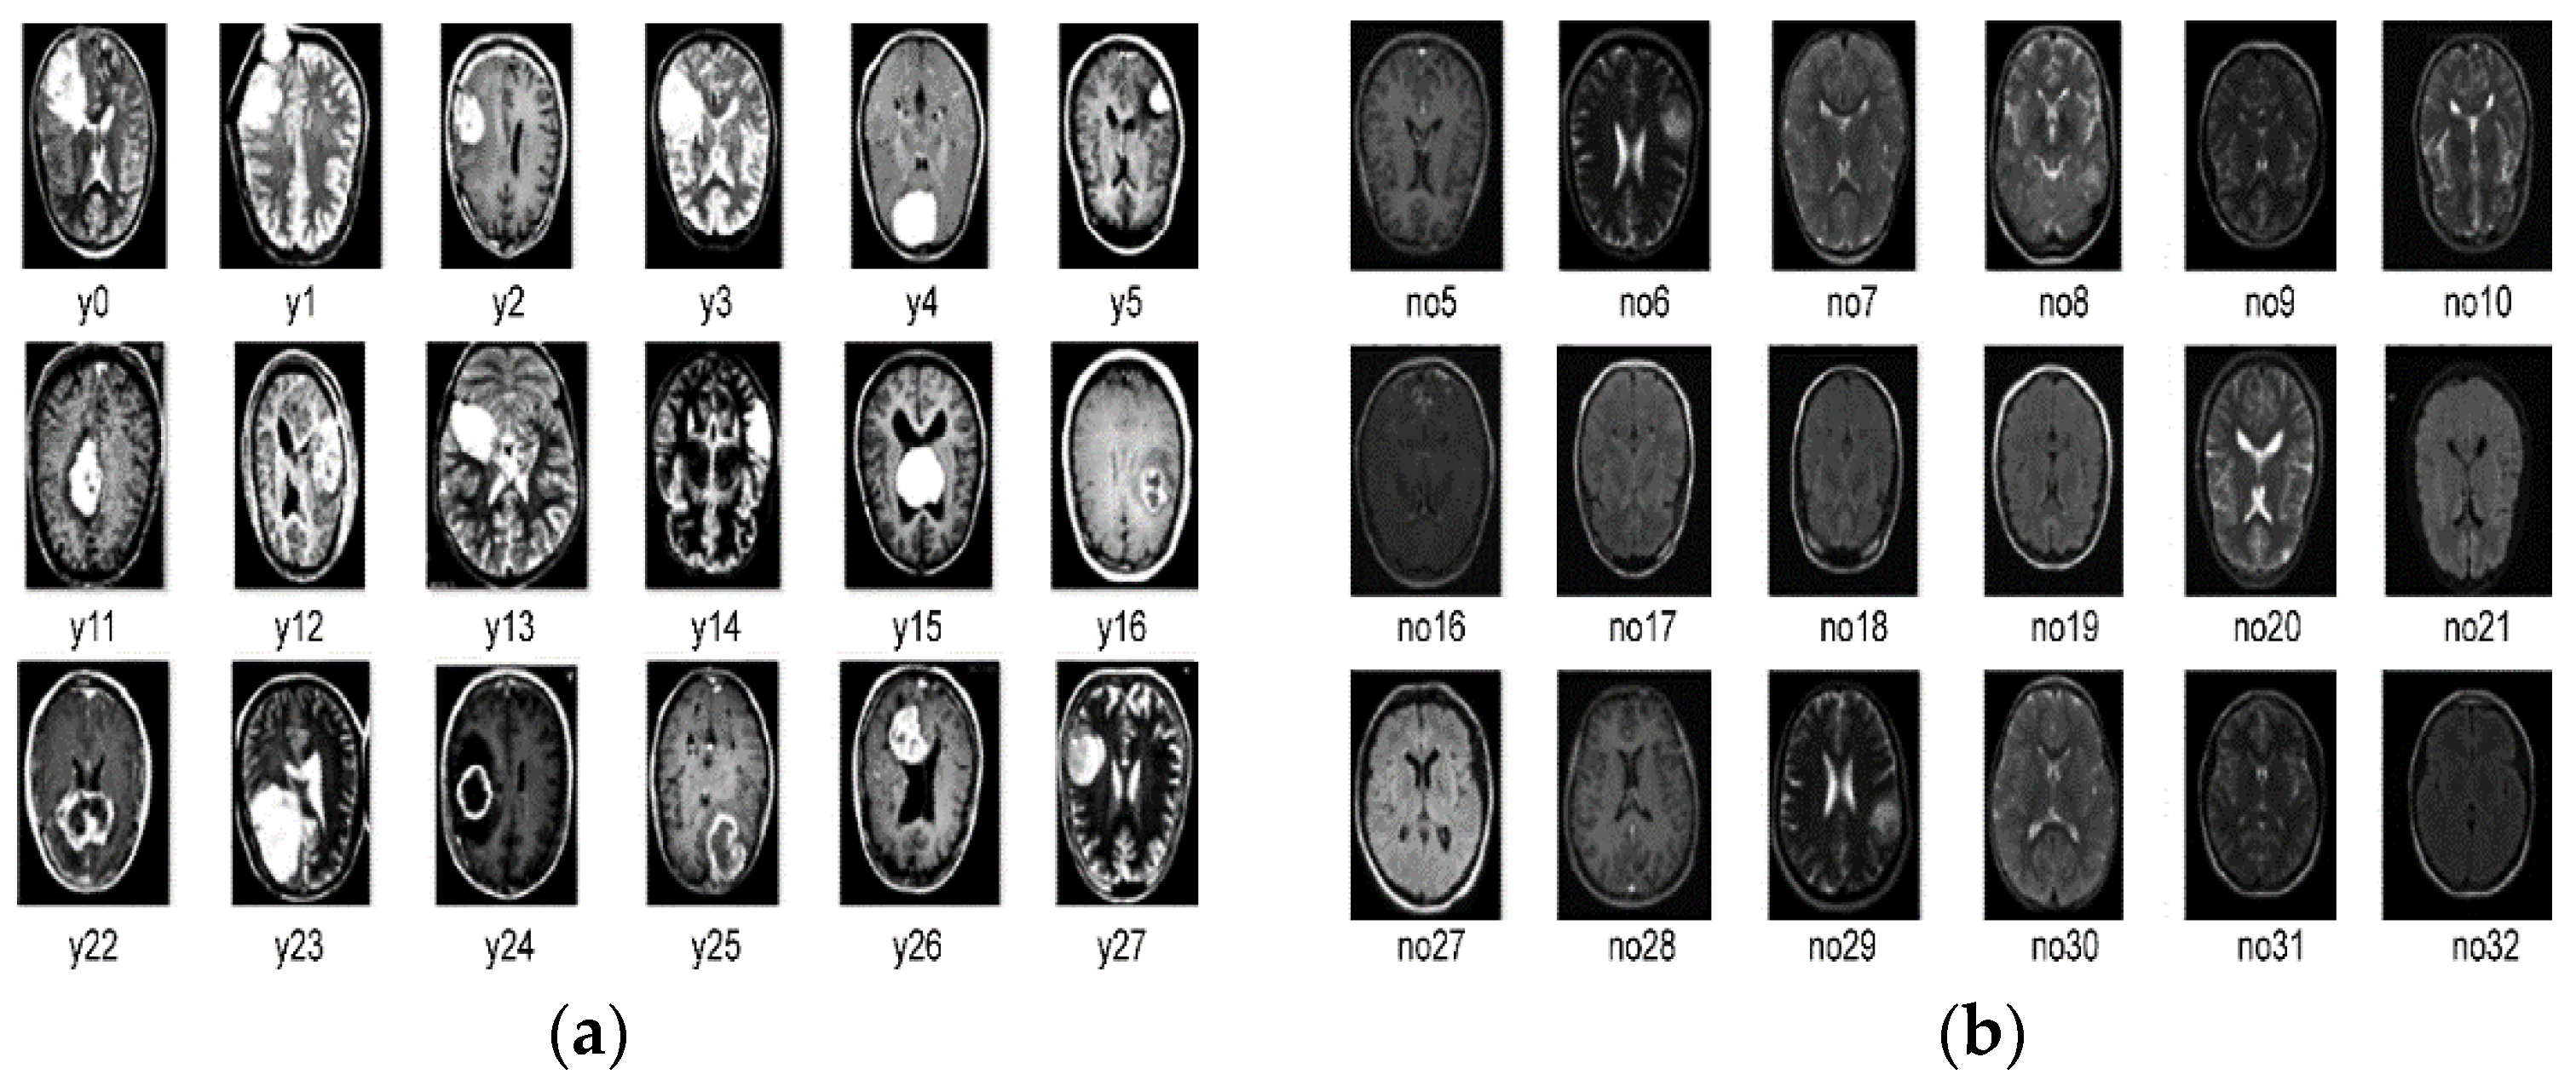

The experiments described in this study were performed by utilizing a publicly accessible dataset acquired from a Kaggle (Br35H) [59]. This dataset consisted of 1500 brain MRI images with tumors and 1500 brain MRI images without tumors. All images were two-dimensional and had a height and width of 256 × 256 pixels. All images were skull-stripped and labeled yes if they contained a tumor and no if they did not. Figure 1 shows the dataset of images with and without tumors labeled yes and no, respectively. The descriptions of the training and testing datasets are listed in Table 1, Figure 3 and Figure 4.

Figure 3.

MRI images of two categories: (a) with tumor (b) without tumor.